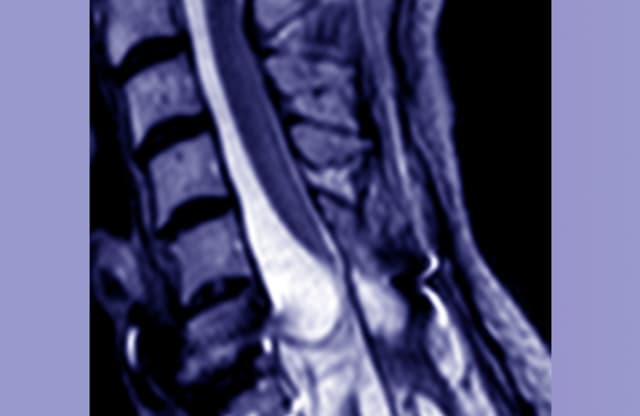

imageSchwere akute Rückenmarkverletzung im Bereich der Halswirbelsäule. Bild: © Charité | Marcel Kopp